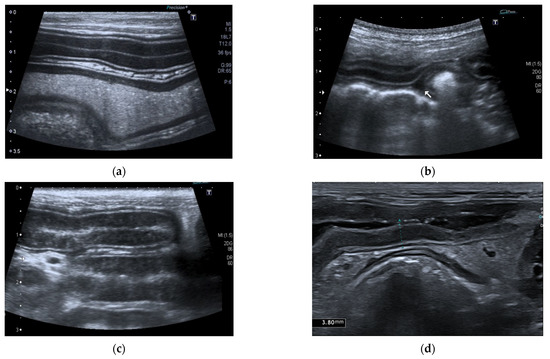

Successful Management of a Pancreatic Abscess in a Dog with Juvenile Diabetes Mellitus Through Ultrasound-Guided Drainage and Medical Therapy

by Alexandra Daravigka, Stefanos Ninis, Panagiotis Bourdekas, Alexandros O. Konstantinidis, Argyrios Ginoudis, Katerina K. Adamama-Moraitou, Maria Lyraki and Nektarios Soubasis

A five-month-old female mixed-breed dog presented with a two-week history of polyuria, polydipsia, and vomiting. Clinical examination revealed poor body condition, growth retardation, pale oral mucous membranes, weak pulse, and prolonged capillary refill time. Laboratory findings included neutrophilic leukocytosis with a regenerative left [...] Read more.

A five-month-old female mixed-breed dog presented with a two-week history of polyuria, polydipsia, and vomiting. Clinical examination revealed poor body condition, growth retardation, pale oral mucous membranes, weak pulse, and prolonged capillary refill time. Laboratory findings included neutrophilic leukocytosis with a regenerative left shift, fasting hyperglycemia, elevated fructosamine, glycated hemoglobin, and β-hydroxybutyrate concentrations, while the acid–base balance remained normal. Canine-specific pancreatic lipase and trypsin-like immunoreactivity concentrations ruled out an underlying pancreatitis or exocrine pancreatic insufficiency, respectively. Urinalysis showed glycosuria and ketonuria. Supportive care included antibiotics and regular insulin administration. Abdominal ultrasonography identified a pancreatic cavity with a thick wall and mixed echogenic fluid. Ultrasound-guided drainage was performed without complications. Cytology confirmed a pancreatic abscess with pyogranulomatous inflammation, though the culture results were negative. The dog was discharged with intermediate-acting lente insulin. Follow-up ultrasonographic evaluations at 7, 14, and 21 days and 5 months post-drainage showed no recurrence. The diabetes remained well-controlled one year post-discharge. This case report describes the successful management of a dog with juvenile diabetes mellitus complicated by a pancreatic abscess, highlighting the effectiveness of percutaneous ultrasound-guided drainage combined with medical therapy. Full article

Show Figures

Figure 1